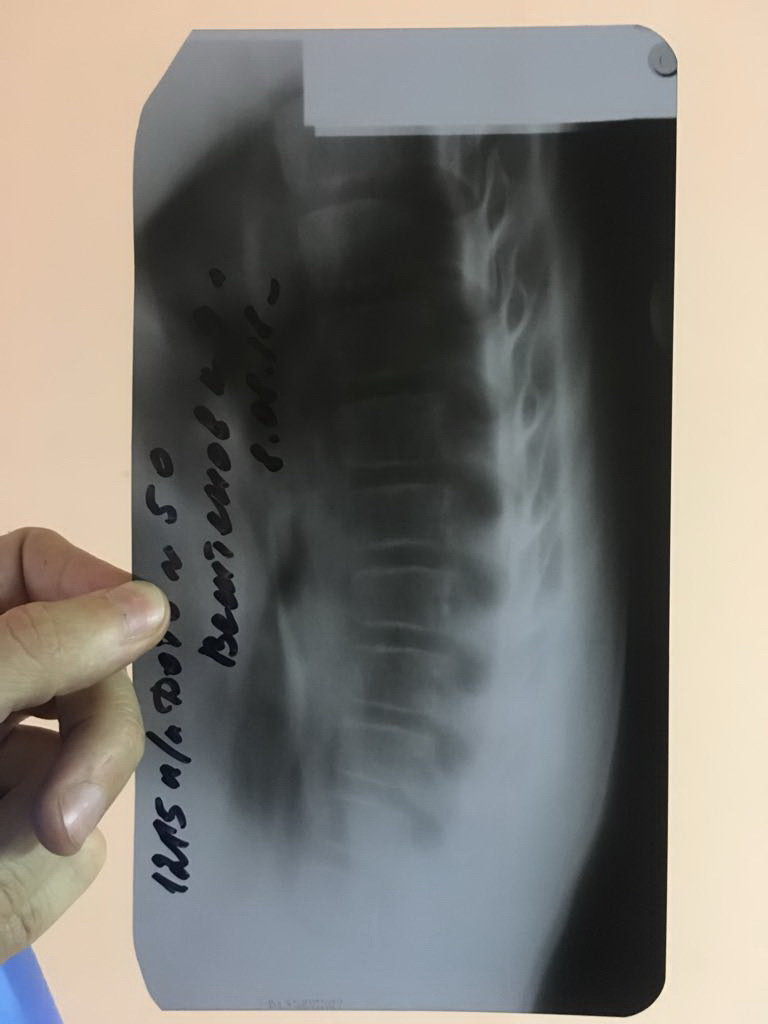

Рентгеновские снимки и медицинские изображения компрессионных переломов